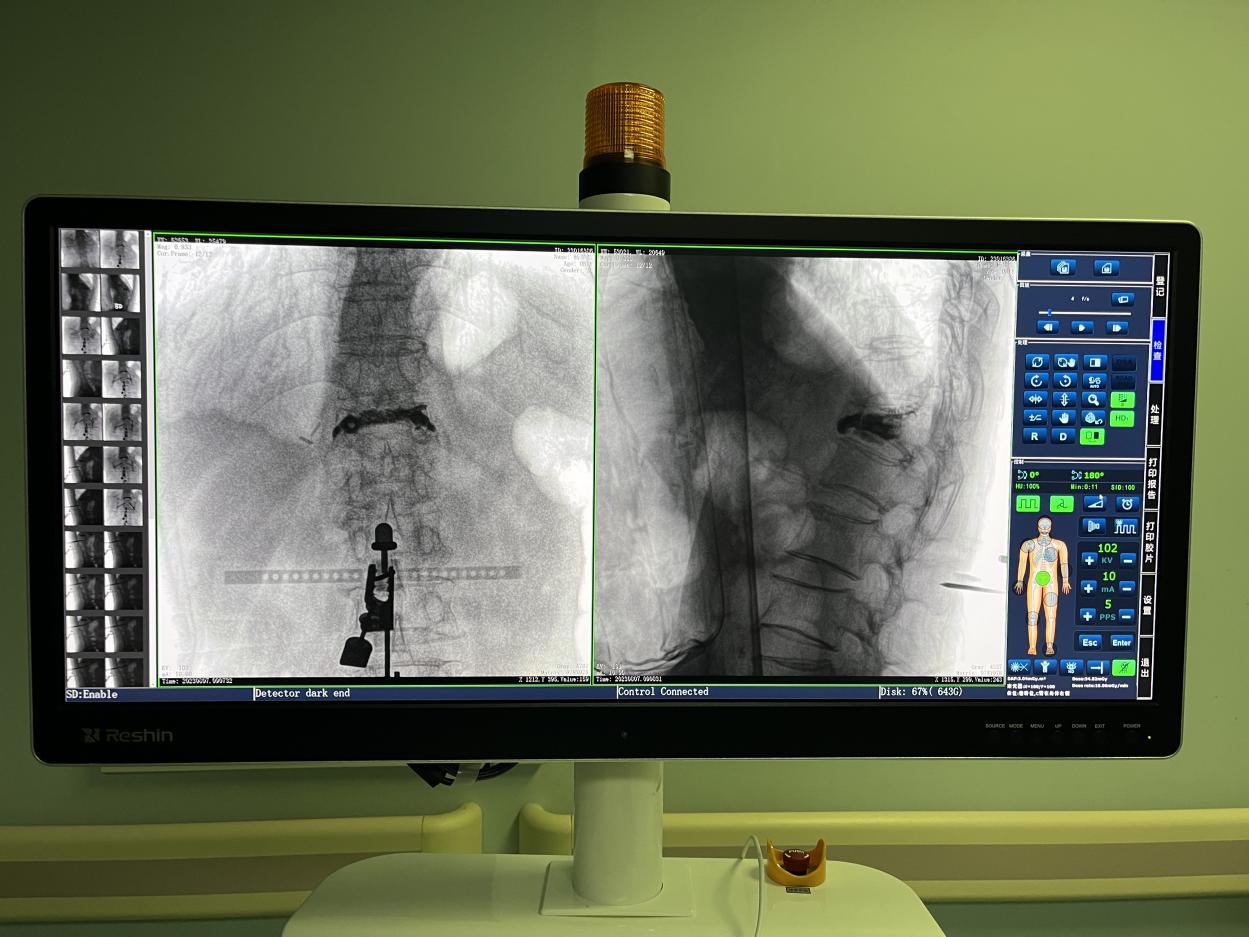

PL300B搭配华体会体育登入首页自主研发生产的平板三维C形臂使用,通过三维立体术中图像,手术医生可从各个方位观察合适的手术入路,并进行关键数据测量,从而最大限度地避开危险区。

骨科机器人手术-术中影像